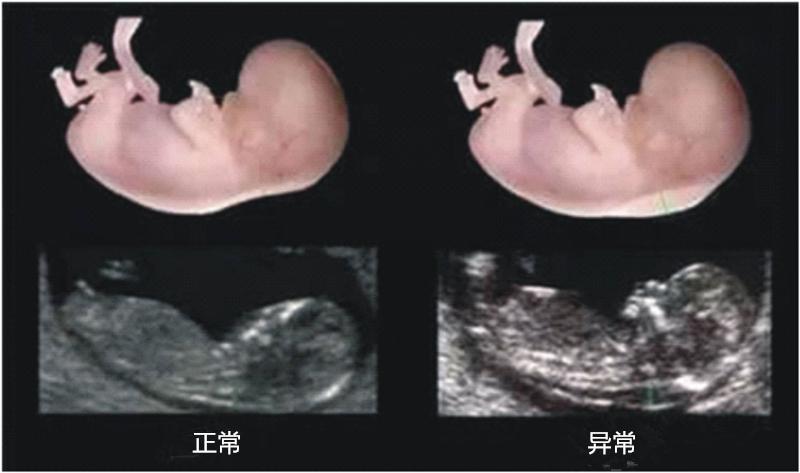

观察nt全景图

通过观察NT全景判断胎儿性别也被认为较为准确:生殖器特征:如果NT单上有显示圆圆的东西,这个有很大概率是男宝宝的生殖器,说明孕妈妈怀的是男孩;其他特征:如果NT单上有显示有三个白线或一个小凹槽说明孕妈妈怀的是女孩。